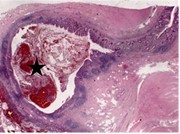

Transitional cell carcinoma arising in a tailgut cyst

Adnan A. Sheikh and others

Journal of Surgical Case Reports, Volume 2015, Issue 7, July 2015, rjv085, https://doi.org/10.1093/jscr/rjv085